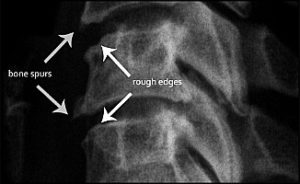

Osteophytes indicate age of the problem, not age of the person. We’ve seen spurs in people in their early 30s, and no spurs in people in their 60s. If a spinal joint moves out of alignment and becomes stuck, the clock starts ticking. It may take several years before the first indicator, a roughened edge on the vertebra, begins to show up.

Somewhere around 3 – 5 years following the start of the spur, you can actually see it on x-ray and recognize it as a bony osteophyte. With each passing year, we see spinal degeneration and the associated bone spurs show up in younger and younger patients.